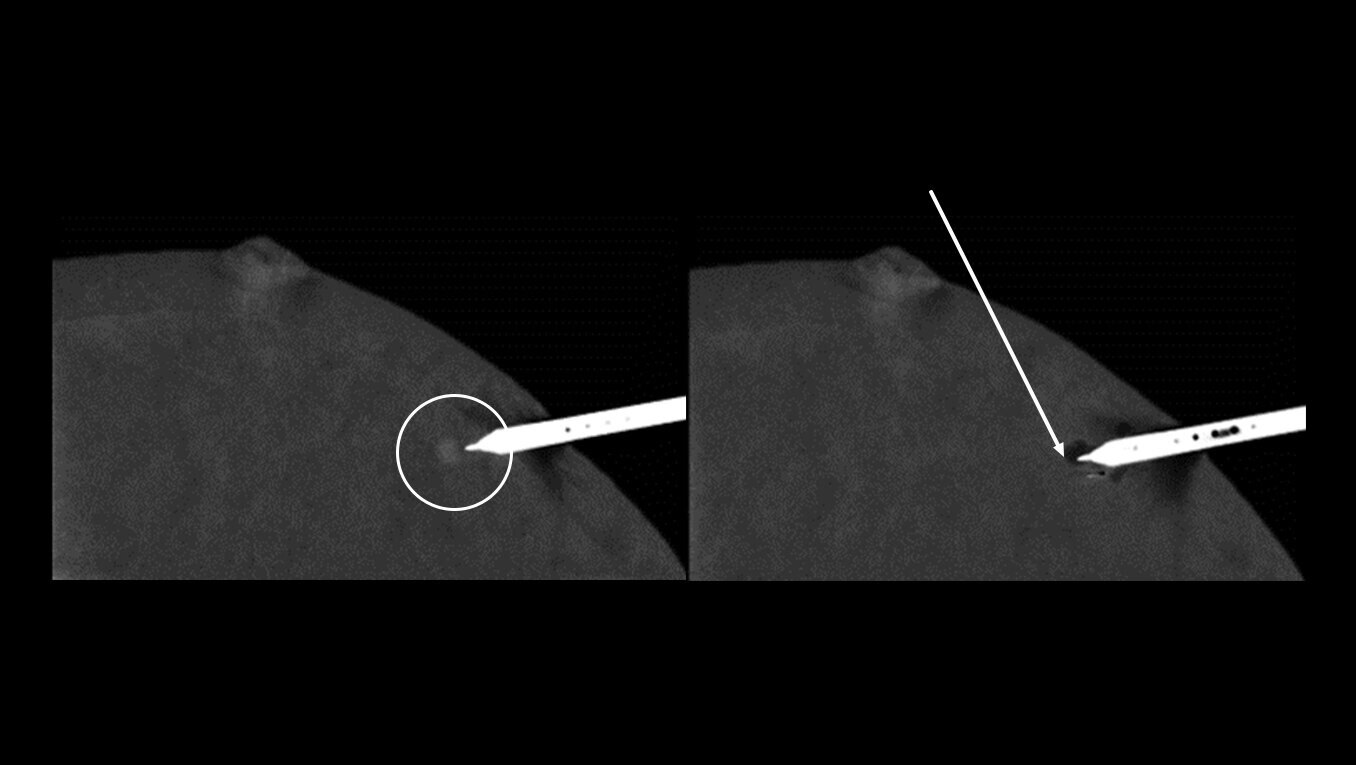

Fast procedure

CEM biopsy can be done within 15 minutes1.

Switch to interventional on the same system within your current room in 2 minutes4.